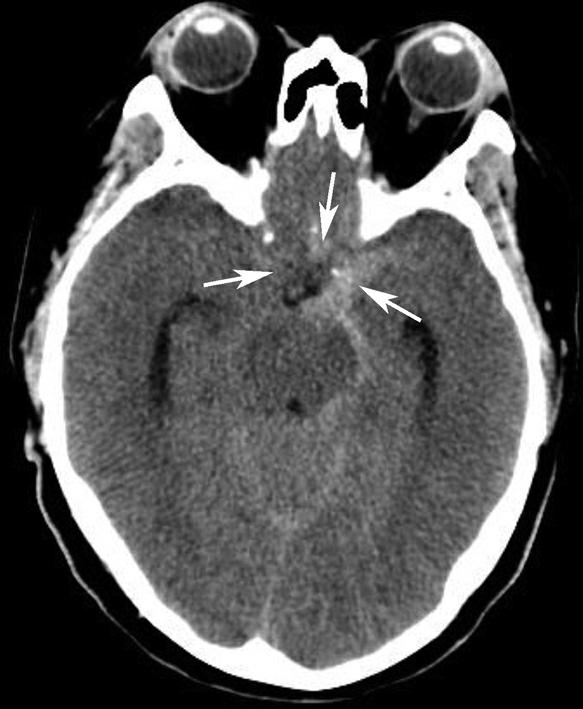

基底动脉开窗畸形的发生机制被认为是胚胎第5周时成对的胚胎性神经动脉融合障碍,或为原始侧动脉残留所致(图1-2-78)。

图1-2-78 基底动脉开窗畸形(箭)

永存三叉动脉是颈内动脉海绵窦段与基底动脉之间的胚胎性吻合,为颈内动脉系统与椎基底动脉系统之间最常见的异常交通,是根据它伴行的颅神经而命名的。其他异常吻合包括永存听动脉、永存舌下动脉及永存寰前节间动脉(图1-2-79)。

图1-2-79 永存三叉动脉

A、B.异常吻合支沟通至右侧海绵窦(箭);基底动脉(长箭)